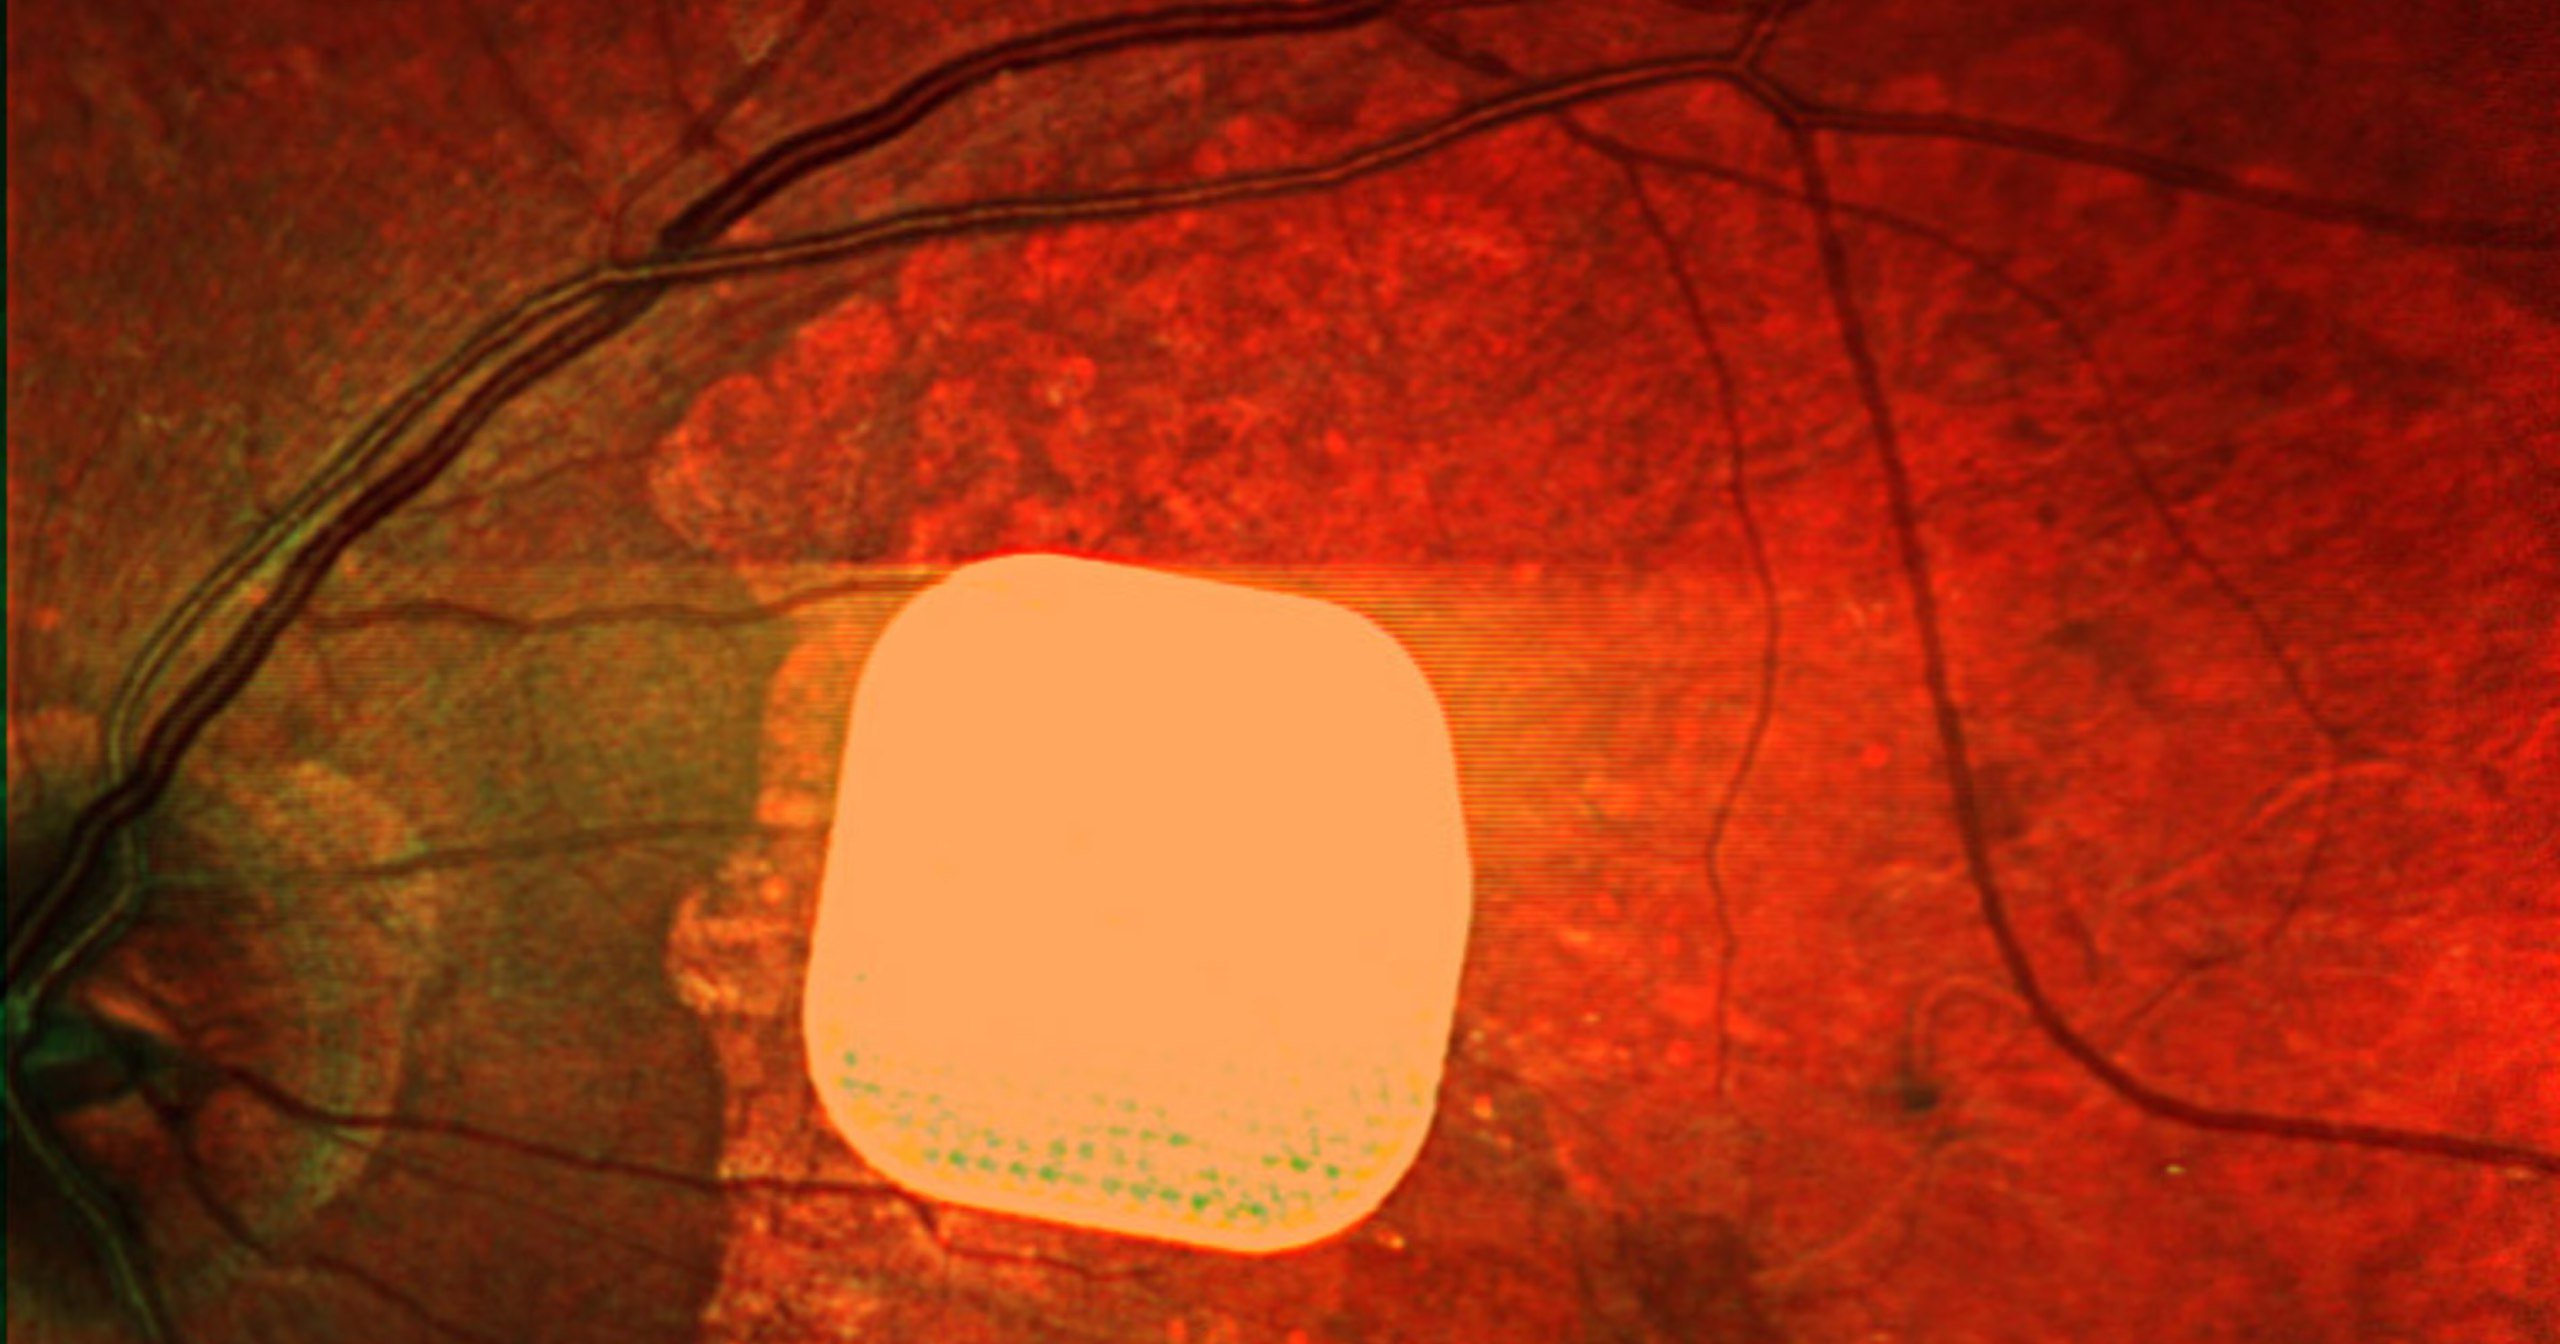

Імплант Prima – це мікрочип розміром 2×2 міліметри, який хірургічно розміщують під сітківкою ока. Під час операції, що триває менш як дві години, пацієнту встановлюють пристрій, який потім працює разом із окулярами доповненої реальності.